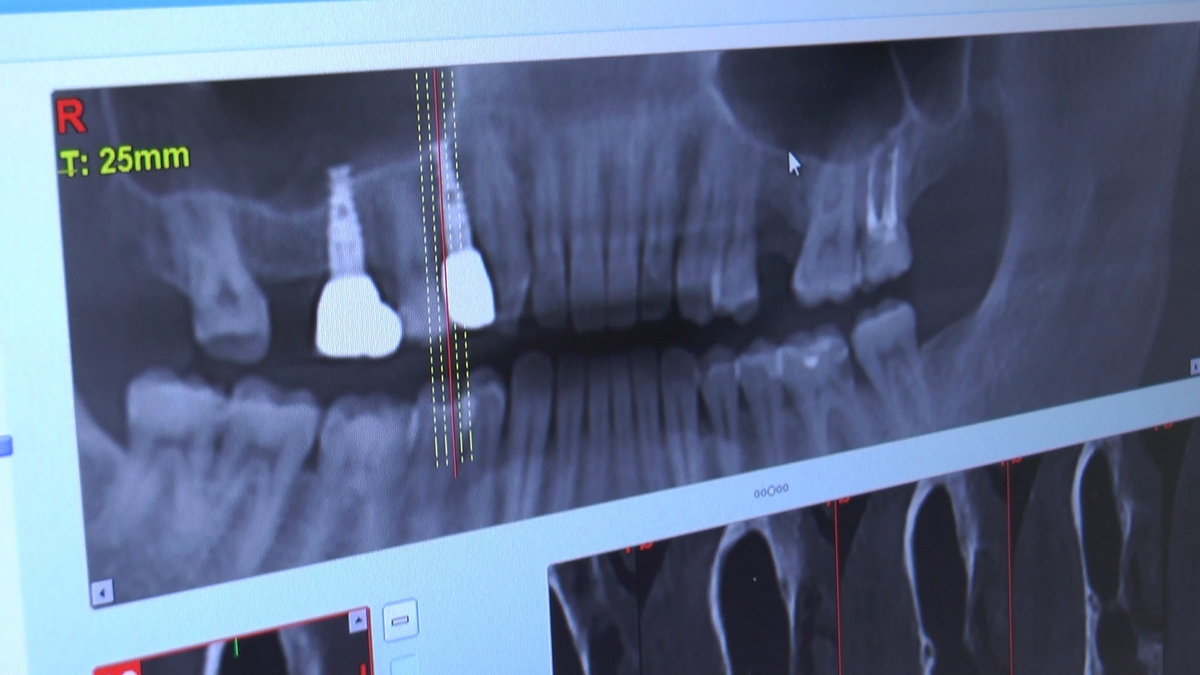

W trakcje dwóch dni zabiegowych, piątek i sobota, 5 i 6 października 2018 roku, lekarze uczestniczący w 6 Sesji VI Sezonu, wykonali wiele zabiegów o wysokim stopniu trudności. Przeprowadzili je pod kierunkiem Mentorów Instytutu Vivadental – dr n.med. Violetty Szycik, dr n.med. Magdaleny Kisłowskiej-Syryczyńskiej oraz dr Małgorzaty Piotrowskiej.

Wprowadziliśmy łącznie 25 implantów w tym wykonaliśmy:

dwa zabiegi All- on -4 / jeden w szczęce, jeden w żuchwie/ z usunięciem zębów i natychmiastową implantacją oraz natychmiastową odbudową protetyczną